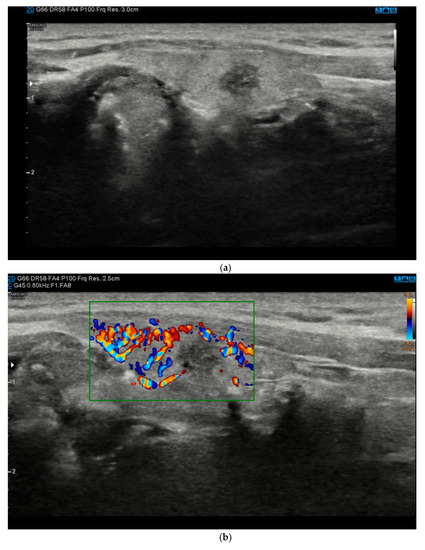

Figure 1.

(a). At B-mode Ultrasound (US), the lesion appeared round-shaped, hypoechoic with irregular margins (EU-TIRADS 5). (b). At color–Doppler US evaluation, the lesion showed no internal or peripheral vascularization (pattern I). (c). At US-Elastography (USE) evaluation, the lesion appeared stiff (ECI: 4.03). (d). At S-Detect evaluation, the lesion suggested intermediate suspicion of malignancy (TIRADS 4). Finally at histology it was identified as a papillary carcinoma.